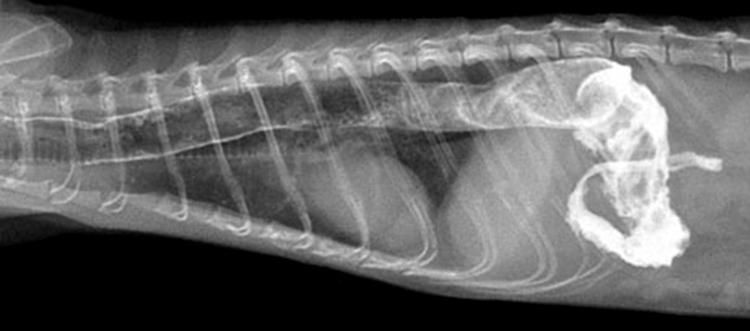

鑑別診断には食道または胃腸の異物、胃炎、および呼吸器疾患が含まれます。X線検査では食道が拡張あるいはガスが貯留しており、確定診断のために硫酸バリウムまたはイオヘキソール(経口投与 [PO] で 8~10 mL/kg)を投与します。フェレットは注射器で強制的にバリウムを摂取しますが、食道破裂の可能性がある場合には、バリウムの代わりにイオヘキソールを使用します。造影剤が食道の輪郭を描出し、巨大化していることで診断されます。

造影剤が食道全体に浸潤しているような像が得られると食道炎を併発している可能性が高いです。

フェレットの巨大食道症の原因は、先天性や食道炎など上げられていますが、詳細は不明です。自己免疫性重症筋無力症は2頭のフェレットで報告されていますが、いずれのフェレットにも巨大食道症の兆候は見られませんでした〔Antinoff 2015,Couturier et al.2009〕。食道内異物であれば外科手術または内視鏡的摘出術でうまく治療されています〔Caliguiri et al. 1989,Webb et al.2017〕。

食道狭窄が報告されており、内視鏡的バルーン拡張術と食道ステント留置術で修正されている報告があります〔Ramsell et al.2010〕。